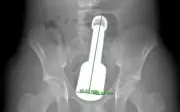

Bệnh viện Đa khoa Hà Đông vừa can thiệp thành công, lấy dị vật kim loại dài 18cm ra khỏi trực tràng bệnh nhân 15 tuổi mà không cần mổ phanh, bảo tồn chức năng tiêu hóa.